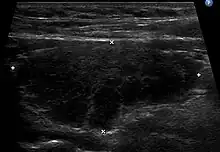

Diagnosis is usually made by detecting elevated levels of antithyroid peroxidase antibodies in the serum, but seronegative (without circulating autoantibodies) thyroiditis is also possible.[54] An ultrasound may be useful in detecting Hashimoto thyroiditis, especially in those with seronegative thyroiditis, due to key features detected in the ultrasound of a person with Hashimoto's thyroiditis, such as "echogenicity, heterogeneity, hypervascularity, and presence of small cysts."[55]

Ultrasound

When patients have normal laboratory values but symptoms of autoimmune thyroiditis, ultrasound plays a role in diagnosis.[16] Images obtained with ultrasound can evaluate the size of the thyroid and further support the diagnosis of autoimmune thyroiditis, reveal the presence of nodules, or provide clues to the diagnosis of other thyroid conditions.[16]